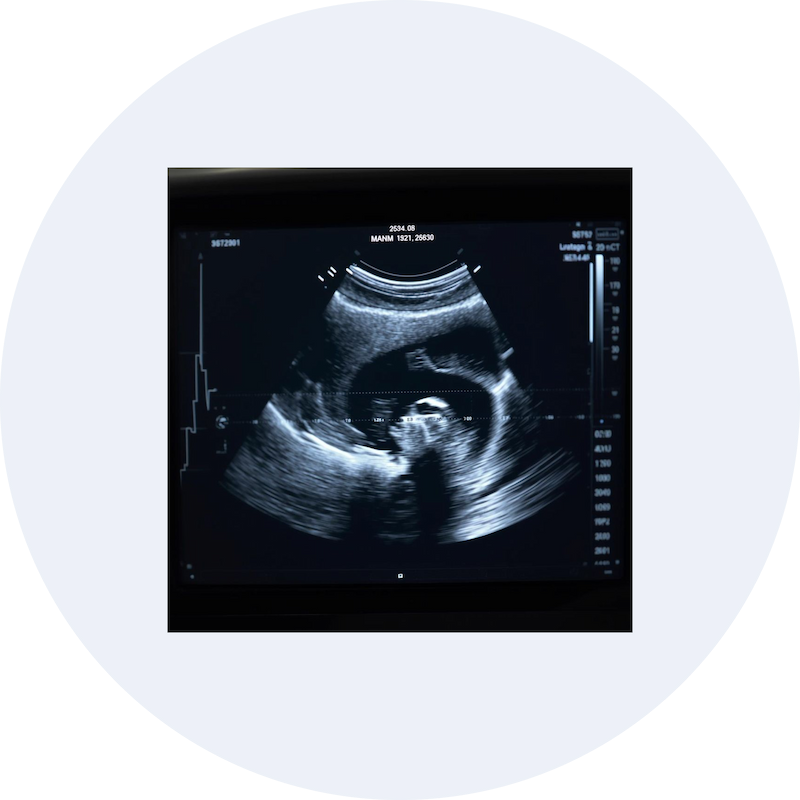

Ultrasound (sonography) scan image displayed on a monitor for diagnostic imaging

At our diagnostic facility, sonography scans are performed using modern ultrasound equipment by experienced doctors for proper clinical interpretation.